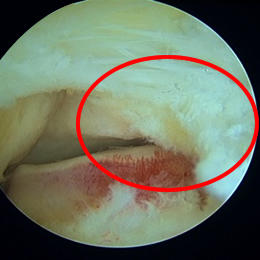

保存療法では痛みが取れない場合には、手術療法が選択されます。手術では主に内視鏡を使用して三角骨の摘出、並びに長母趾屈筋腱の腱鞘の切開を行っています。

内視鏡の手術では腹臥位(うつ伏せ)で行います。アキレス腱の両側に7mm程度の傷をつけるだけで手術を行うことができます。手術中に足関節後方の滑膜炎の程度(痛み具合)や長母趾屈筋腱の障害の程度を評価し、一人一人の状態に合わせたリハビリを行っていきます。平均して10日~2週間程度入院します。退院後も再発しない様に、体の正しい使い方などを指導していきます。

![]() 三角骨による圧迫 |

![]() 長母趾屈筋腱腱鞘を開放した後 |